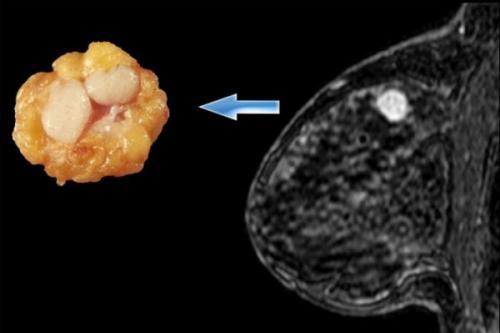

называют фиброаденоматоз (представлен на фото).

Эта патология характеризуется быстрым разрастанием железистой ткани с образованием кист, заполненных жидкостью.